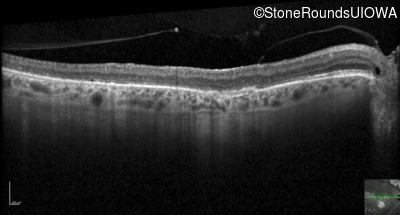

Optical Coherence Tomography - Left - 20/80

Exemplar / OCT Stack